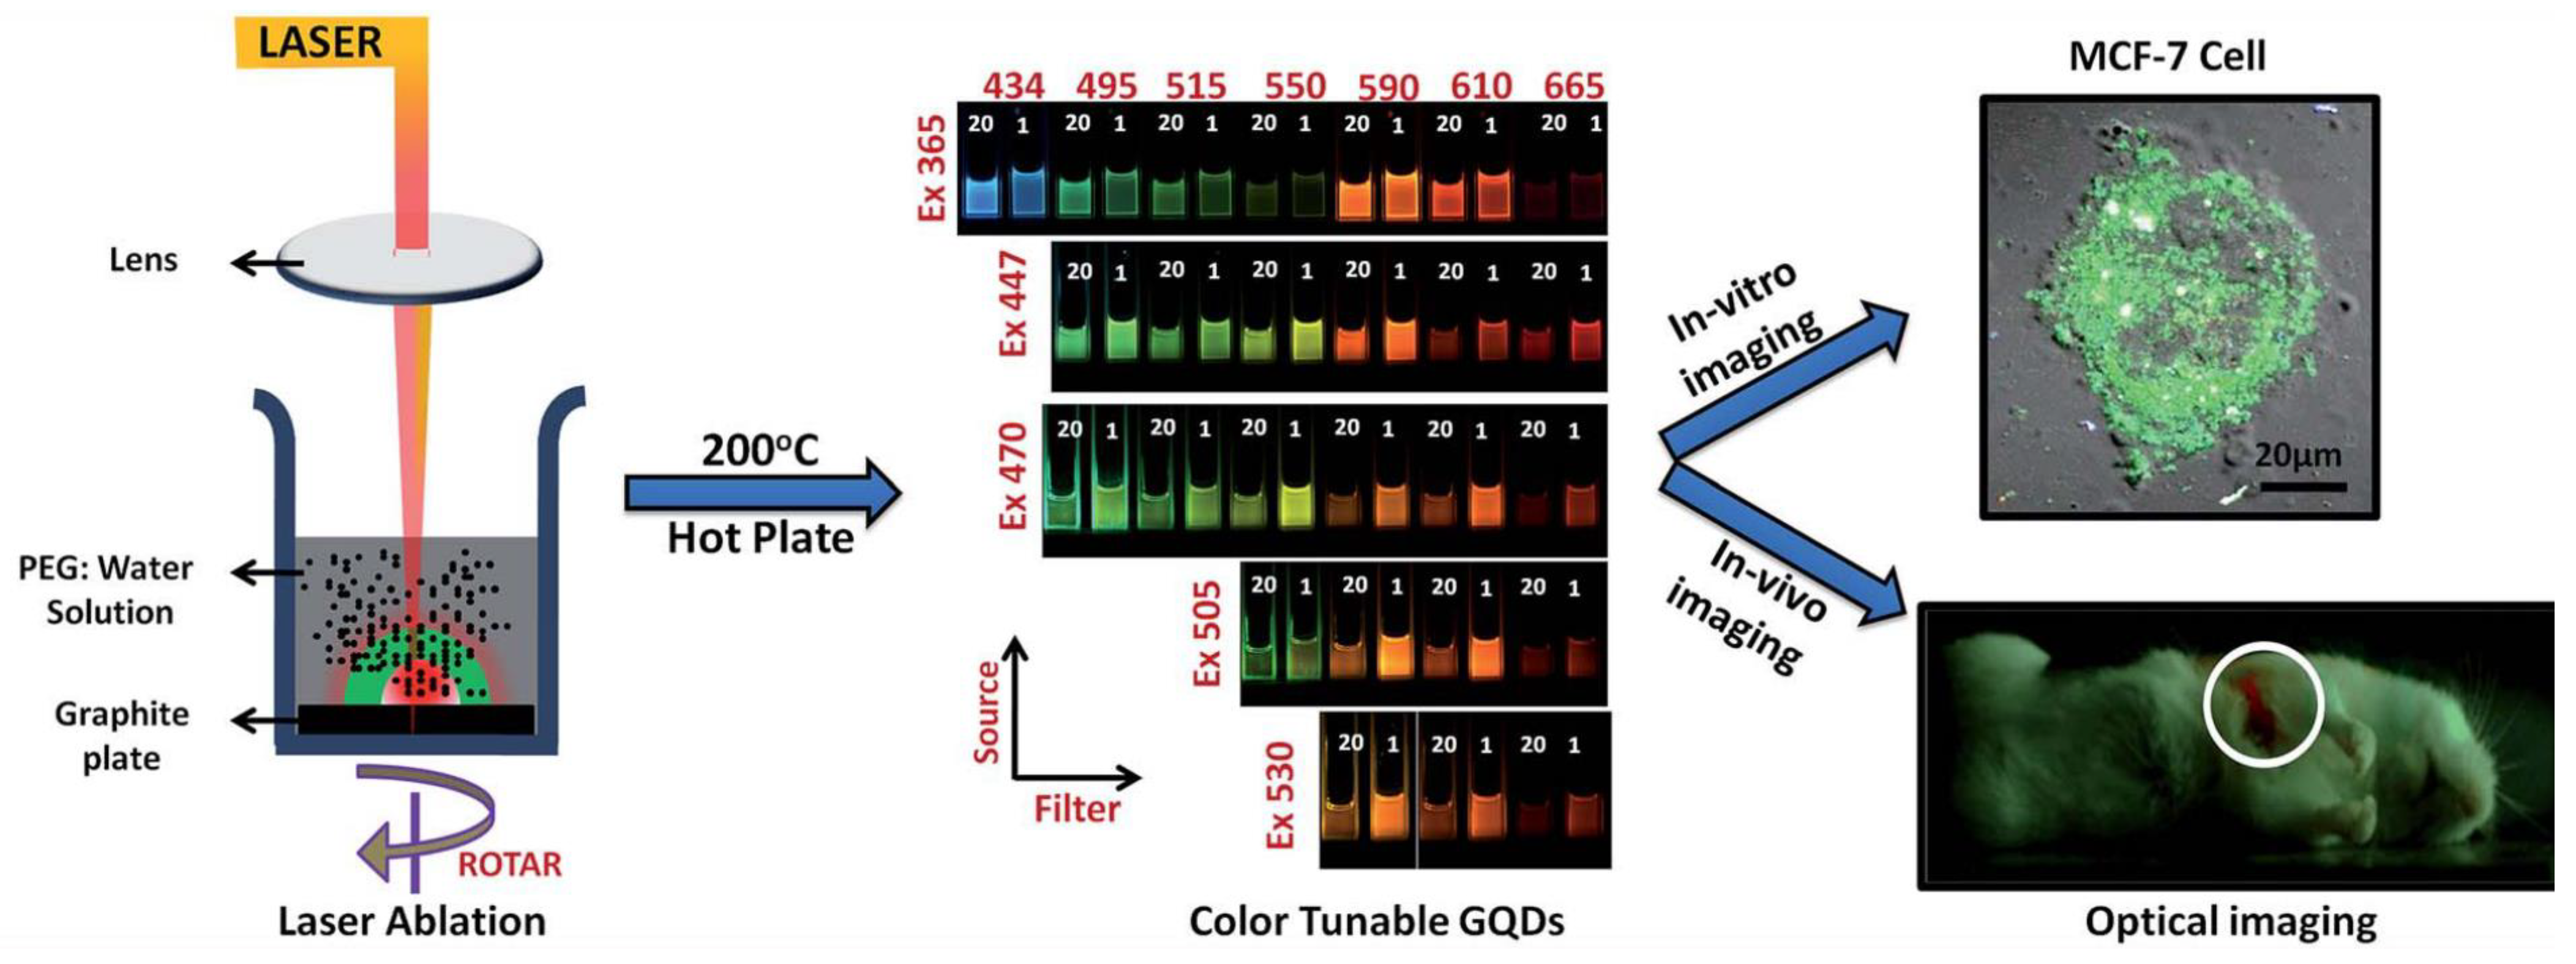

3.2.6. Extending PLAL Technique

4.1. Bio-Applications

- Narasimhan, A.K.; Lakshmi, B.S.; Santra, T.S.; Rao, M.S.R.; Krishnamurthi, G. Oxygenated graphene quantum dots (GQDs) synthesized using laser ablation for long-term real-time tracking and imaging. RSC Adv. 2017, 7, 53822–53829. [Google Scholar] [CrossRef]